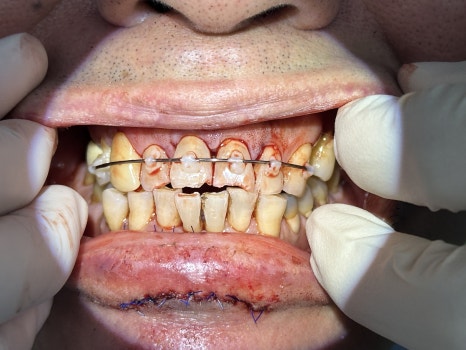

즉시 치아 재위치 후, 레진-와이어 스플린트로 고정

🖼️ 입술 외상 사진 / 앞니 파절 및 고정 사진 / X-ray 사진

외상 직후 찢어진 입술 / 앞니 탈구 고정한 초기 응급처치 사진

🔧 신경치료와 입술 봉합, 중간 치료 경과

앞니의 신경은 이미 괴사되어 있었고,

즉시 신경치료를 통해 감염을 제거하고 치아를 살리는 방향으로 치료를 이어갔습니다.